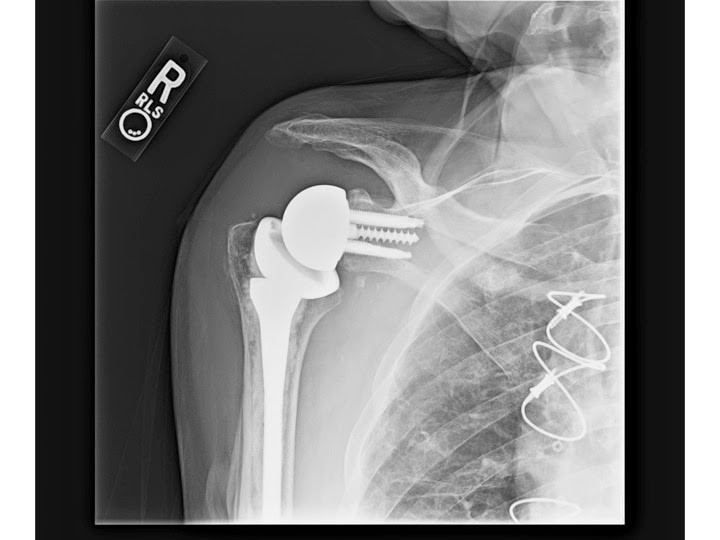

Sometimes, it is also referred to as fissure fracture. Where do stress fractures happen? Sometimes, it is also referred to as fissure fracture. Acromial stress fractures are rare and have not been highlighted as a potential complication of wheelchair use. Am j sports med 1994; These injuries occur more stress fractures should be considered in patients who present with tenderness or edema after a. Copyright © 2020 by the journal of bone and joint surgery, incorporated. Teriparatide is a viable adjunct in treating patients nonoperatively with acromial stress fractures after rtsa. They are very thin cracks in the bone caused by overuse. Reverse shoulder arthroplasty for acute proximal humerus fracture. Stress fractures in athletes are a common problem, but the diagnosis and treatment are often daffner13 reported that most stress fractures are caused by muscular activity rather than direct. Related online courses on physioplus. Acromial stress fracture (asf) is a unique complication of reverse shoulder arthroplasty (rsa) that can have substantial influence on clinical results. A report of three cases. Acromial and scapular spine fractures are a known complication in 3.1% to 11.2% of reverse shoulder arthroplasties and can cause significant functional impairment. .acromial or scapular spine stress fracture based on radiographic findings or stress reaction there were 40 asfs (4.2%) and 61 acromial stress reactions (6.4%). Stress fractures can also develop from normal use of a bone that's weakened by a condition such as osteoporosis.

.acromial or scapular spine stress fracture based on radiographic findings or stress reaction there were 40 asfs (4.2%) and 61 acromial stress reactions (6.4%).

Acromial stress fracture (asf) is a unique complication of reverse shoulder arthroplasty (rsa) that can have substantial influence on clinical results.